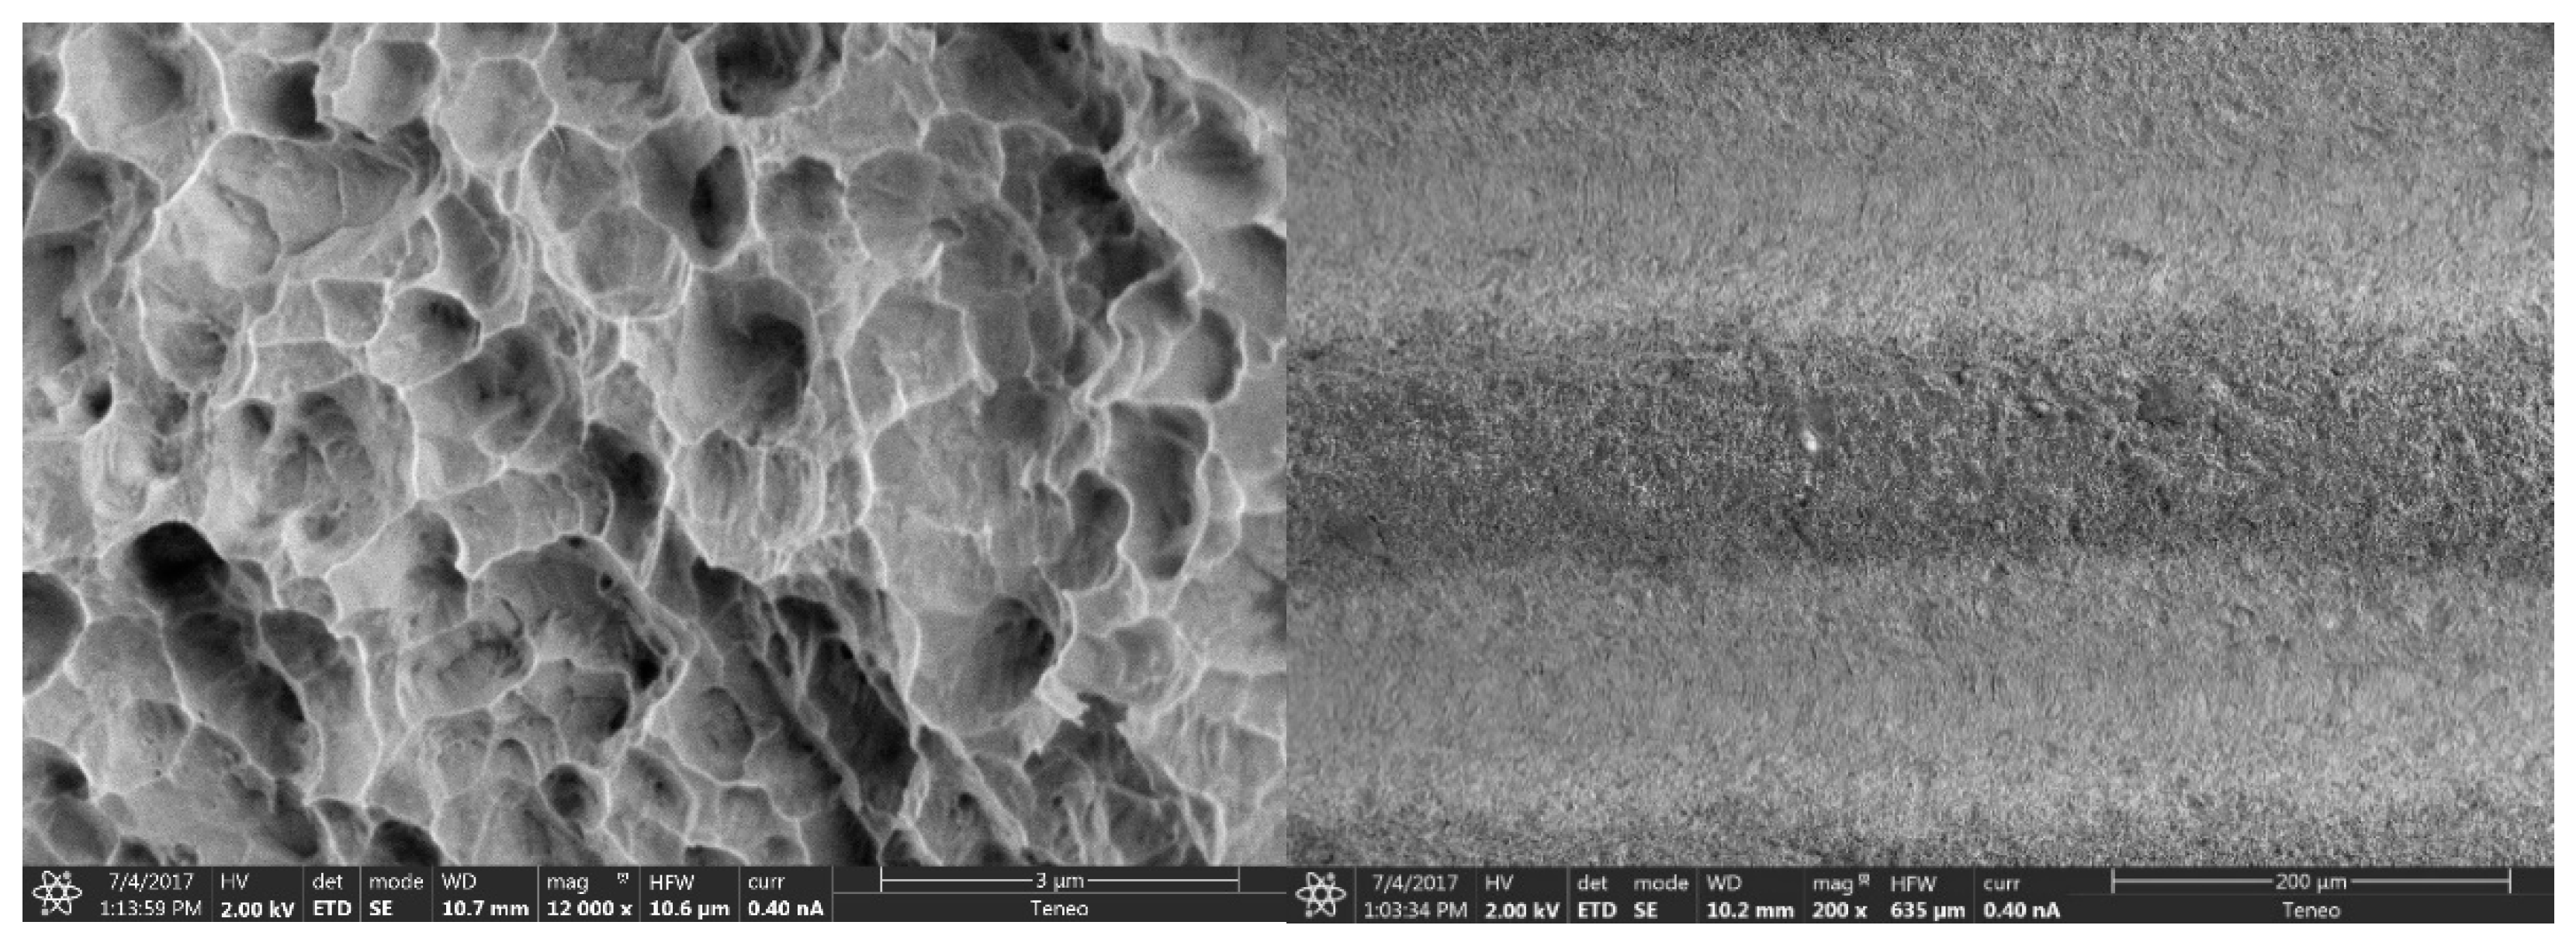

2.2.1. Morphological Analysis of the Surface

3.1.1. Morphological Analysis of the Surface